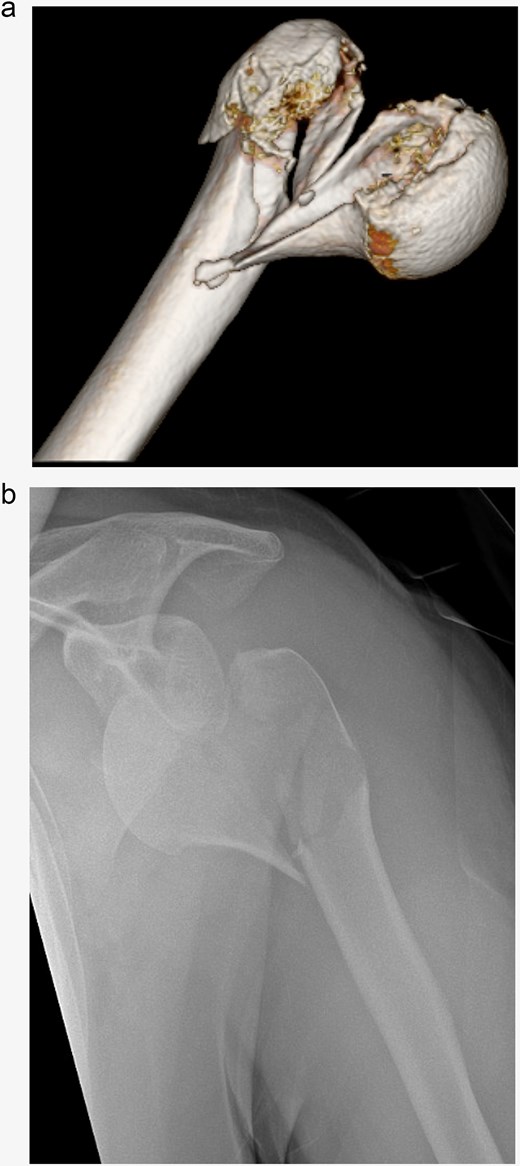

X-rays confirmed a dislocated 4-part proximal humerus fracture AO/OTA 11C3.1. The computer tomography scan demonstrated the presence of a Head-split component in the fracture (Fig. 1). Furthermore, it showed an anteroinferior dislocation of a larger articular surface-bearing fragment and avulsion of the greater tubercle. Neurological examination was intensified to ensure that the recent-onset epileptic seizure had not caused any neurological complications.